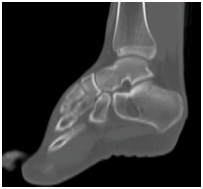

Intraosseous lipomas are diagnosed with plain radiography and CT scan (Figure 1) (Figure 2A) (Figure 2B). Mainstay of treatment is conservative; however surgery is indicated in severe pain not responding to conservative treatment, impending pathological fracture and malignant transformation (Figure 3). Treatment for these tumors is curettage and bone grafting (Figure 4) with good prognosis.8–10

Figure 2 CT Scan of ankle showing lytic lesion in calcaneus.

Figure 2b CT Scan of the foot, axial view, showing lytic lesion.